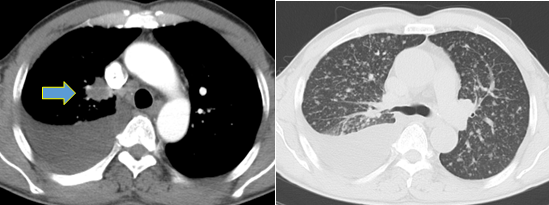

病理检查:(右侧胸腔积液)低分化腺癌。

图片YkT帝国网站管理系统

基因检测:EGFR 19 Del突变